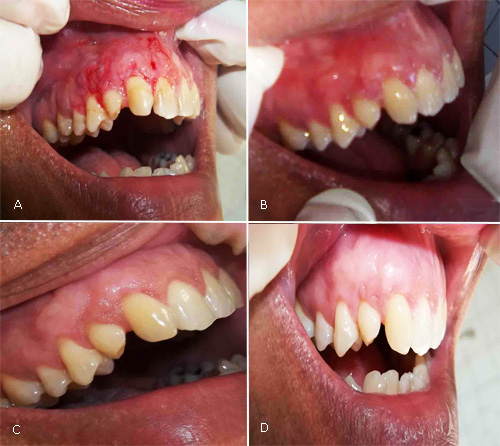

A los 15 días se retiró cemento quirúrgico y suturas del área intervenida. Clínicamente había CR completa del 13, 53 y 14, discreto edema, materia alba y biopelícula. Se orientó cepillar la zona cuidadosamente con cepillo de cerdas blandas y técnica Stillman modificada. Se suspendieron colutorios con clorhexidina (Fig. 3, A).

Al mes, se observó tejido gingival engrosado, raíces totalmente cubiertas, incremento del tejido queratinizado y armonía de color entre zona injertada y área adyacente. Excelente cicatrización del paladar (Fig. 3, B).

A los seis meses había 1 mm de raíz expuesta en 14 y 53, evolución satisfactoria del área receptora y donante (Fig. 3, C).

Al año, existía aspecto estético favorable en zona receptora y CR completa de 13 y 53; 1 mm de raíz expuesta en el 14. Corona clínica del 13 de 10 mm, del 53 de 4,5 mm y del 14 de 9 mm. Incrementó la altura de encía queratinizada (7 mm), verificada con pie de Rey, adecuada inserción clínica de los tejidos, constatada con sonda periodontal (Fig. 3. D).

Fig. 3 - Evolución. A: 15 días; B: 1 mes; C: 6 meses; D: 1 año.